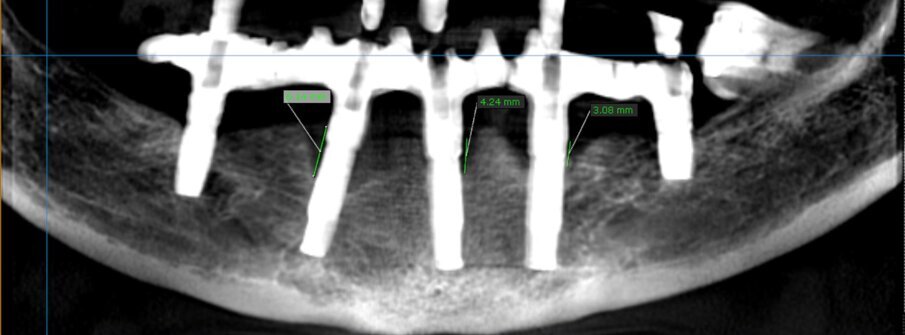

Figure 1. Radiographic assessment at baseline.

Clinical examination revealed 5 implants in the mandible supporting a fixed full arch reconstruction. Probing pocket depths were of the order of 8-9mm around 3 of the anterior implants. The distal implants had normal probing depths. CBCT imaging revealed an intrabony component of 6.1mm for the implant in the 43 position, 4.2mm at the 41 implant and 3.1 at the 33 implant.